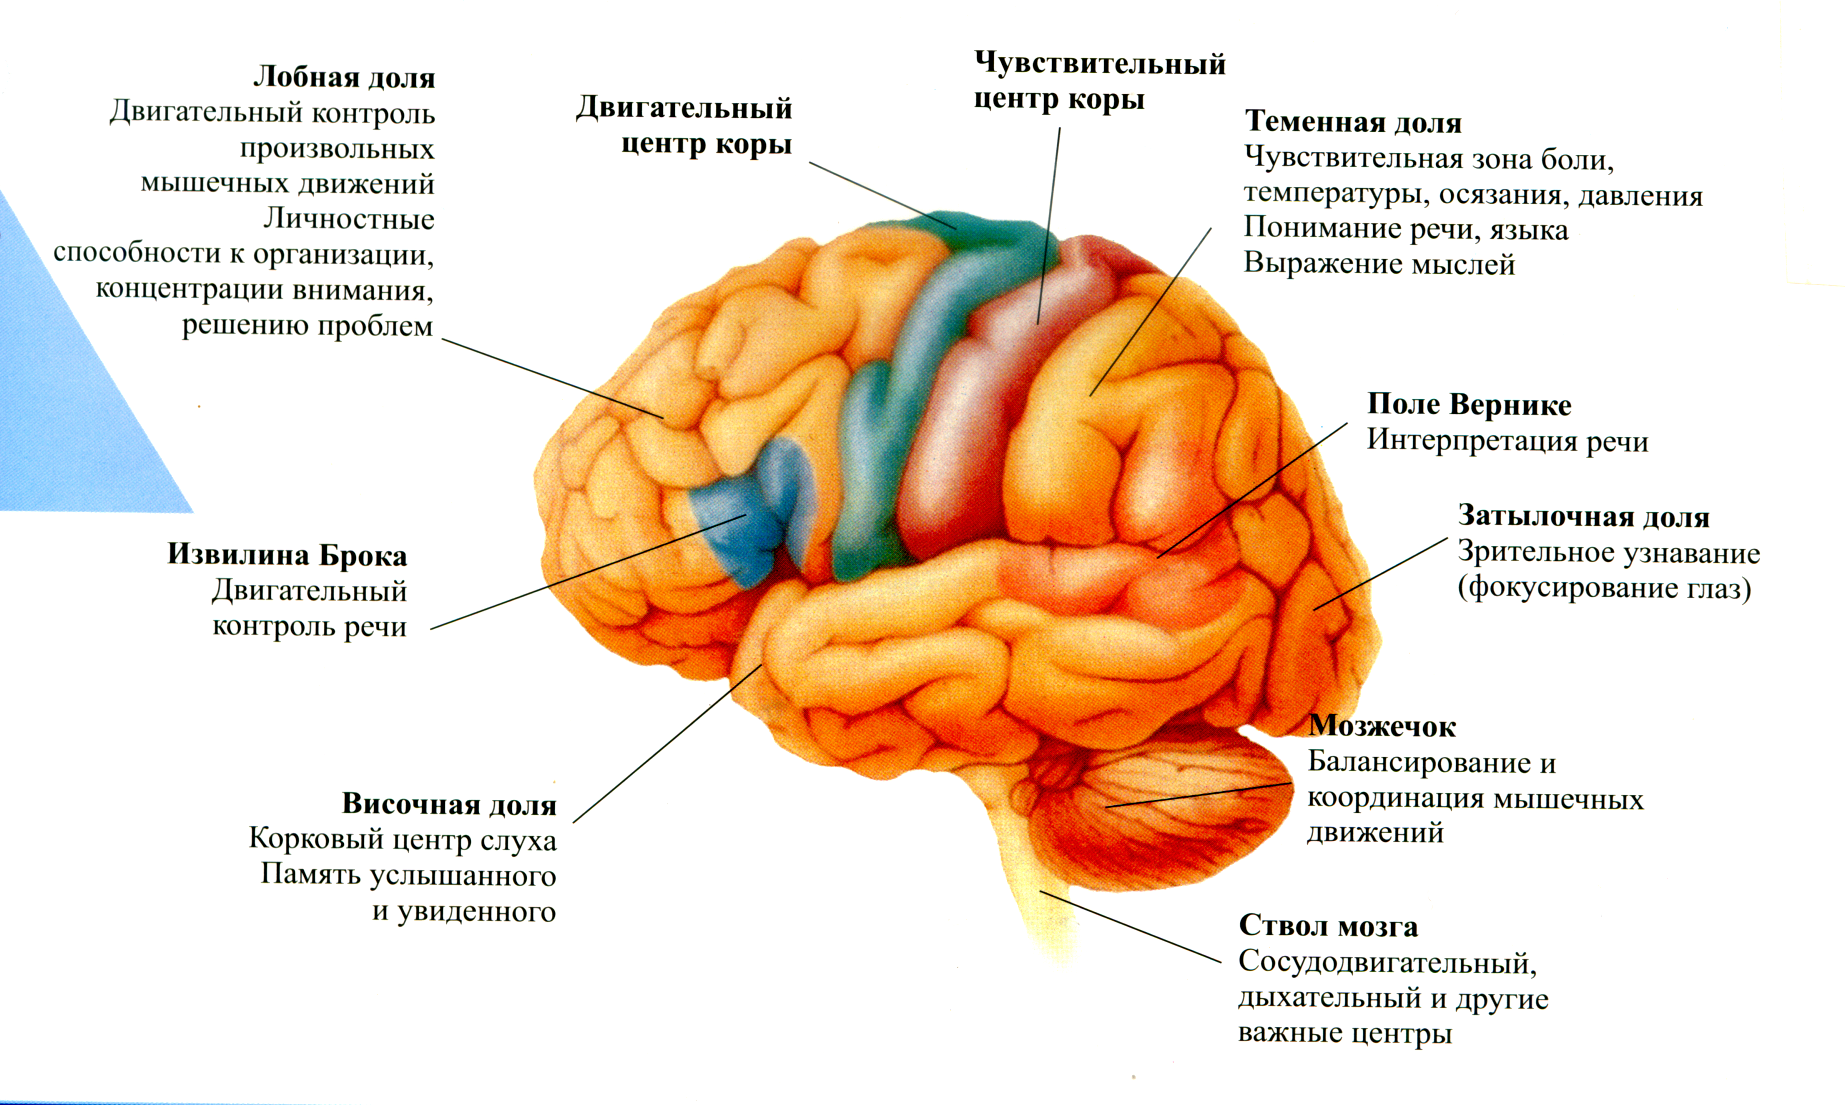

Коннектом мозга: визуализация связей и нейронных путей